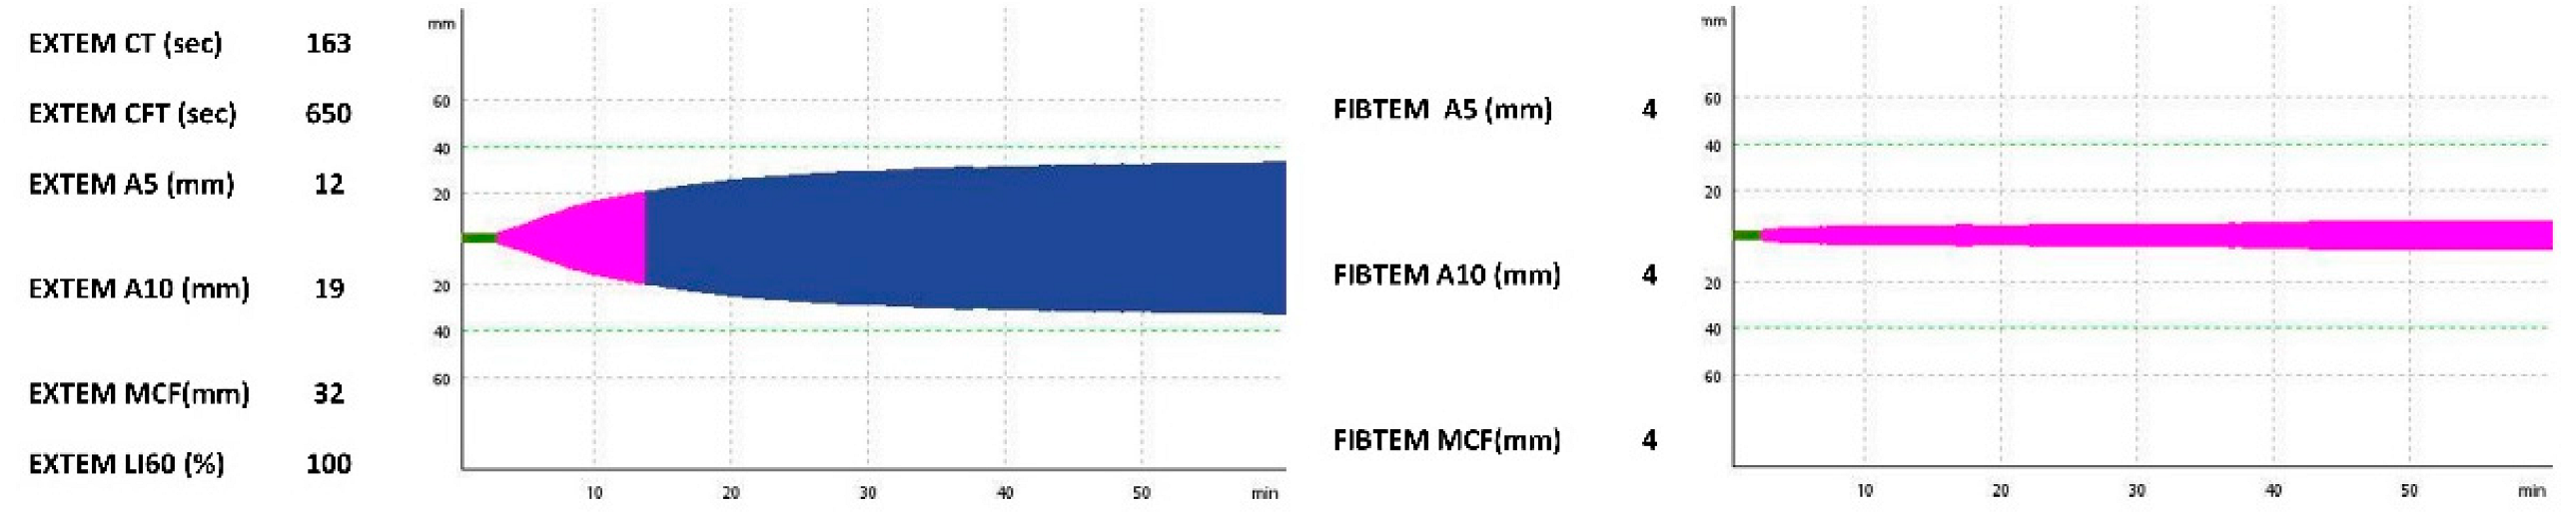

2.2. Case 2

| EXTEM CT (s) | N/A | 128 | 54 | 163 | N/A | 62 |

| EXTEM CFT (s) | N/A | 277 | 190 | 650 | N/A | 87 |

| EXTEM A5 (mm) | N/A | 21 | 26 | 12 | N/A | 42 |

| EXTEM A10 (mm) | N/A | 29 | 37 | 19 | N/A | 53 |

| EXTEM MCF (mm) | N/A | 38 | 48 | 32 | N/A | 58 |

| EXTEM LI60 (%) | N/A | 100 | 100 | 100 | N/A | 98 |

| FIBTEM A5 (mm) | N/A | 5 | 13 | 4 | N/A | 19 |

| FIBTEM A10 (mm) | N/A | 6 | 15 | 4 | N/A | 21 |

| FIBTEM MCF (mm) | N/A | 6 | 20 | 4 | N/A | 26 |